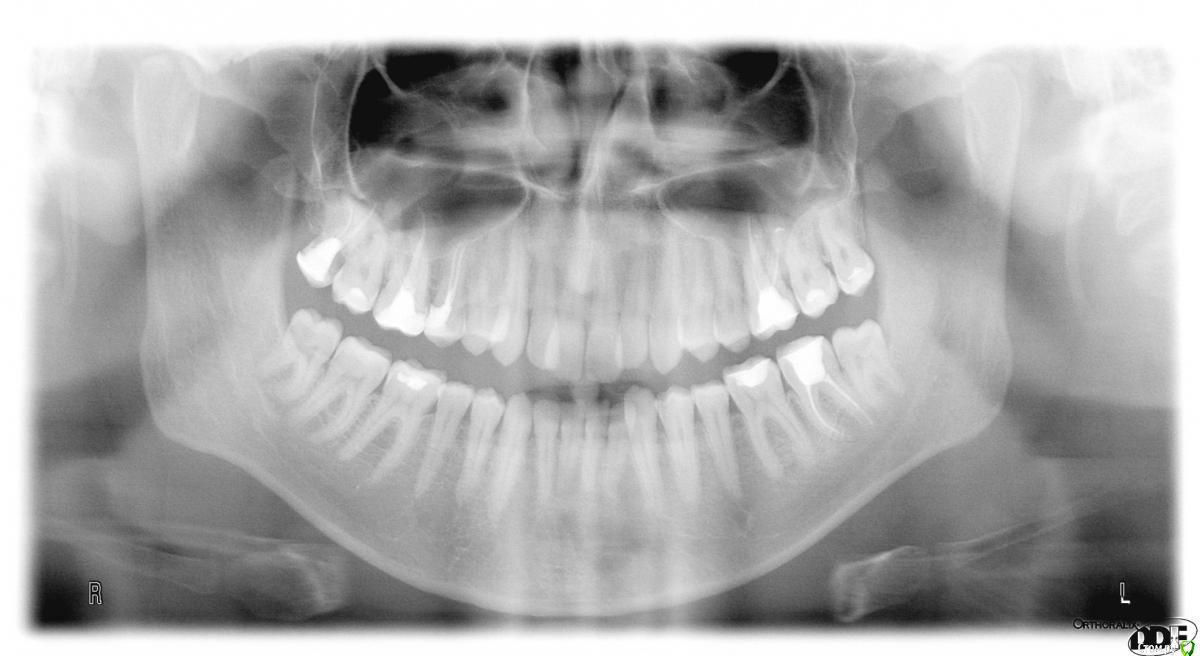

lc_ Опубликовано 22 декабря, 2015 Поделиться Опубликовано 22 декабря, 2015 (изменено) Здравствуйте, эксперты! Мне 27 лет, достаточно давно стоматологи советуют мне обратиться за ортодонтическим лечением. Аргументы приводятся в основном не в силу косметических соображений. 3 года назад я даже было согласился и удалил 2 верхние "восьмерки" (предложением было удалить все 4), но дело до конца не довел. После очередного посещения терапевта, вопрос снова был поднят. Итак, хочу обратиться за консультацией к независимым экспертам: стоит ли устанавливать брекет-систему? Ограничиться просто удалением оставшихся "восьмерок"? Не предпринимать никакие действия и дальше жить спокойно? Спасибо! P.S.Все фото не влезли. Поэтому боковые снимки:http://s020.radikal.ru/i709/1512/be/b7122505b8b3t.jpghttp://s011.radikal.ru/i318/1512/a3/27f5404deddct.jpghttp://s018.radikal.ru/i525/1512/c5/1e3523662a9at.jpghttp://s019.radikal.ru/i634/1512/b7/7bb11e619334t.jpghttp://s015.radikal.ru/i331/1512/45/4e6d94c5b833t.jpg Изменено 22 декабря, 2015 пользователем lc_ Ссылка на комментарий

IvanK Опубликовано 23 декабря, 2015 Поделиться Опубликовано 23 декабря, 2015 Решать Вам) 8ки я бы удалил + Консультация ортопеда о протезировании депульпированных зубов Ссылка на комментарий